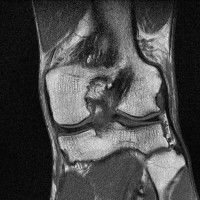

무릎 mri 간단히 봐주실 수 있으시나요 ㅠㅠ

안녕하세요 8년전 십자인대 수술하고 최근 무리한 운동에 무릎 불편감이 생겨서

mri 찍었습니다.

진단결과는 첫 찍은 병원에서 활액막염 이라는 진단을 받았습니다. 혹시 봐주실 수 있으실까요?

올라온 MRI가 단편적이라서 정확한 진단에 어려움이 있지만 십자인대에는 큰 이상이 있지는 않은것 같으며, 무릎관절내 물이 있는 것으로 보아 활액막염의 진단이 맞을 것 같습니다.

하지만 단편적인 영상이기 때문에 촬영병원에서 정확한 판독지 등을 받으시는 것이 좋겠습니다.